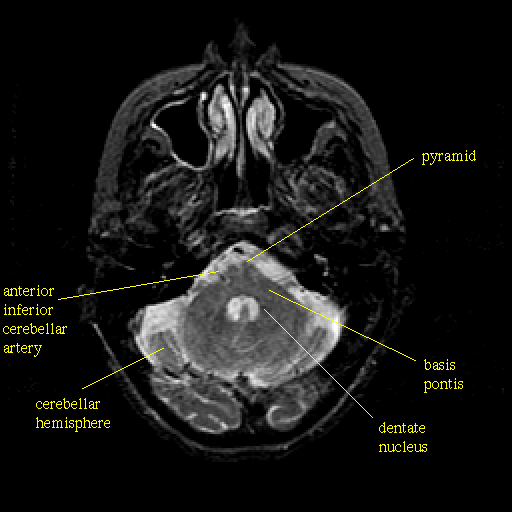

T2-weighted structural MR: Slice 13

Slice 13